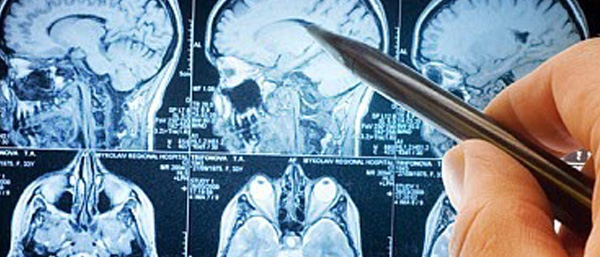

എന്സെഫാലിറ്റിസ് എന്ന് അറിയപ്പെടുന്നത് ഒരു തരം മസ്തിഷ്ക ജ്വരം ആണ്. തലച്ചോറിനെ ബാധിക്കുന്ന കഠിനമായ പനി തന്നെ. തലച്ചോറില് നീര്ക്കെട്ട് പോലെ ഉണ്ടാകും, മരണകാരണം വരെ ആയേക്കുവുന്ന രോഗം. പല രീതികളിലാണ് ഈ രോഗം ബാധിക്കുക. വൈറസ്, ബാക്ടീരിയ, അമീബ എന്നിവ രോഗകാരണം ആകാം. മറ്റ് ചിലപ്പോള് ശരീരത്തിലെ പ്രതിരോധ സംവിധാനത്തിന് പറ്റുന്ന പിഴവും എന്സെഫാലിറ്റിസ് എന്ന മാരക രോഗത്തിന് കാരണമാകാറുണ്ട്.

എത്രയും പെട്ടെന്ന് മികച്ച് ചികിത്സ ലഭ്യമാക്കുക എന്നത് മാത്രമാണ് ഈ രോഗത്തിന്റെ കാര്യത്തില് ചെയ്യാനുള്ളത്. ആദ്യം ഏത് തരത്തിലുള്ള രോഗമാണ് ബാധിച്ചിരിക്കുന്നത് എന്ന് തിരിച്ചറിയണം. അതിന് ആവശ്യമാണ് ഒട്ടനവധി പരിശോധനകള് ലഭ്യമാണ്. ചില രോഗികളില് ചികിത്സയും കാര്യമായി ഗുണം ചെയ്യാറില്ല എന്നതാണ് വേദനിപ്പിക്കുന്ന സത്യം.